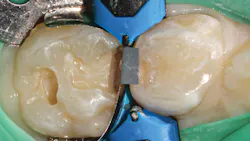

In this case, a W3 ivory rubber dam clamp is placed on tooth A to be restored with an intracoronal restoration. Adjacent tooth B will be restored with a prefabricated pediatric zirconia crown (NuSmile; figure 1). A Hedy rubber dam with a slot style is placed extending from tooth A to the mesial of tooth C.

Once preparation and removal of the infected dentin is achieved, a sectional matrix and ring system (Composi-Tight 3D XR, Garrison Dental Solutions) is used. Taking particular care at the gingival margin, proper matrix placement will ensure control over leakage and any possible contamination, which is important for long-term success (figure 2).